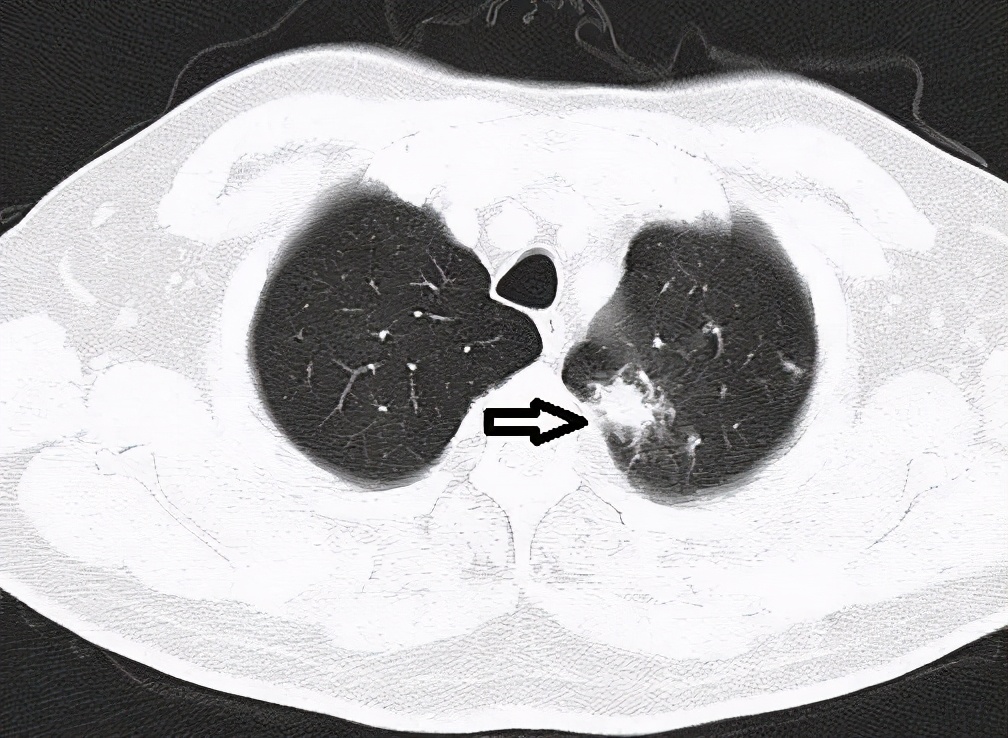

Sarah's lung scan